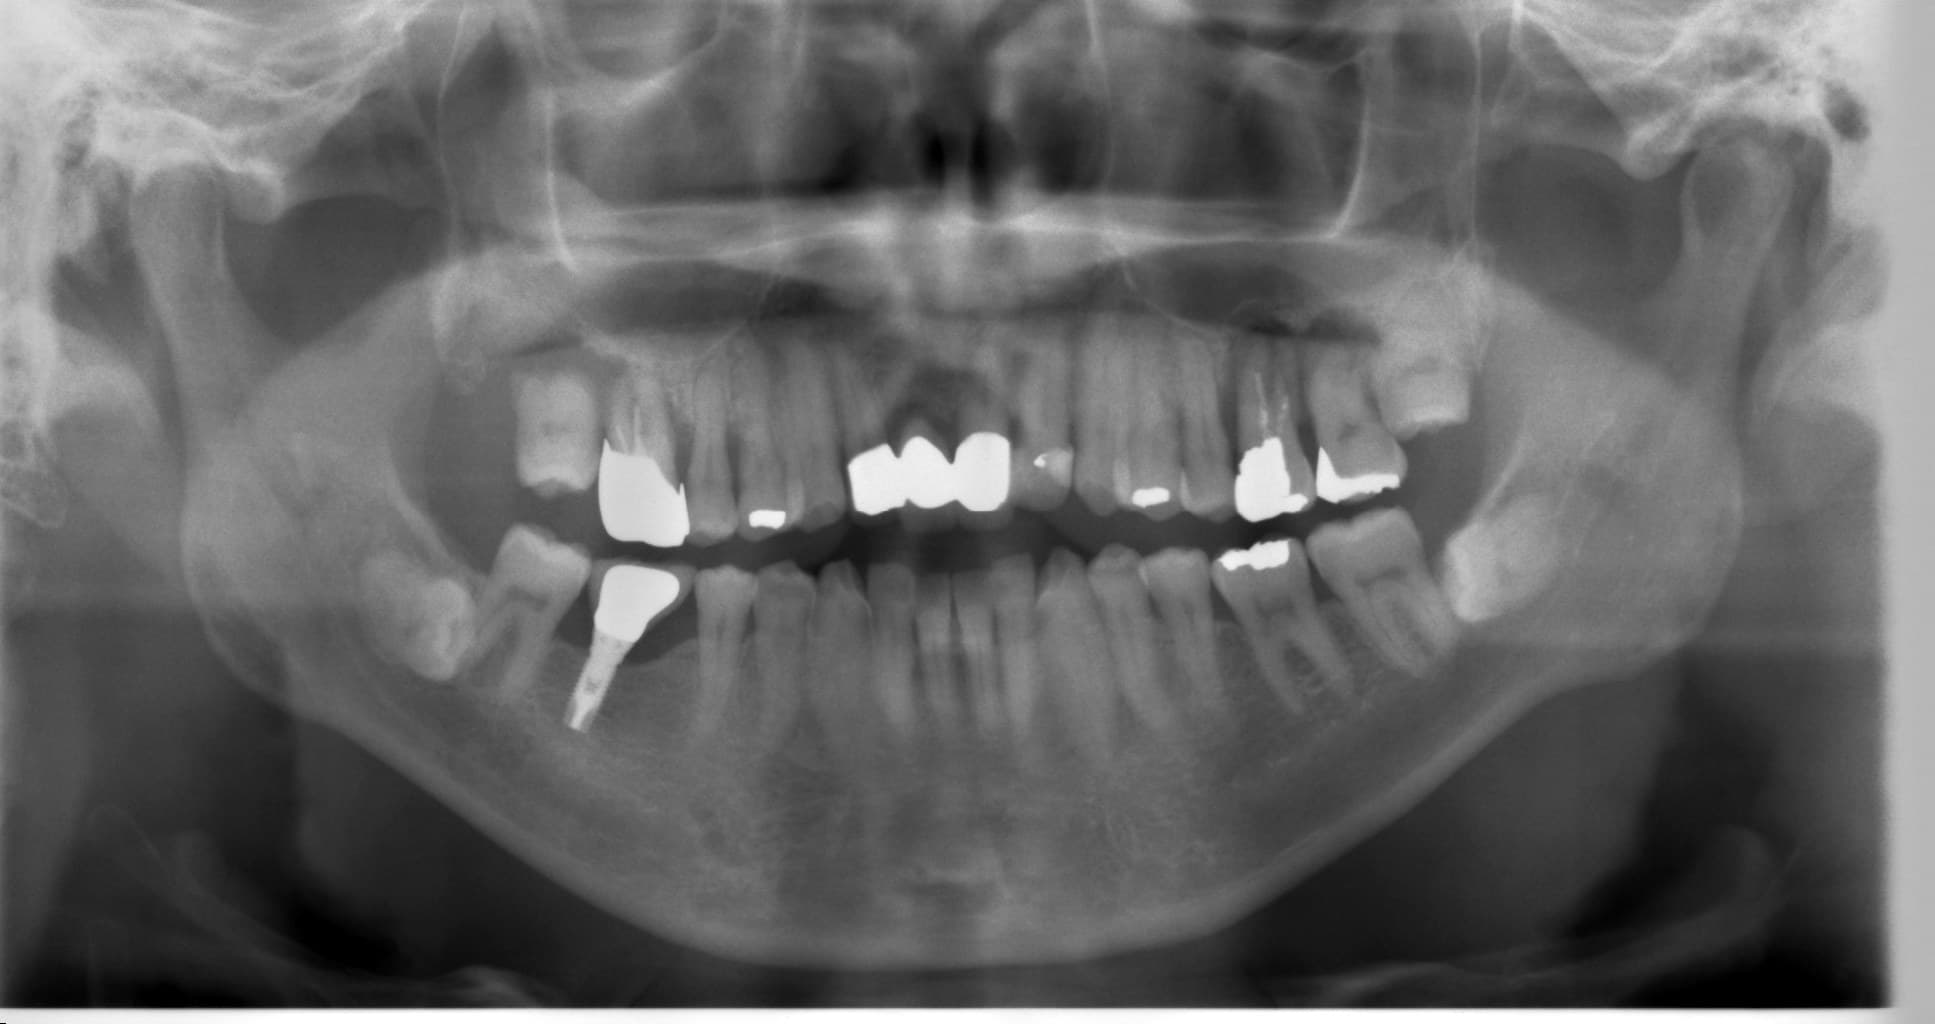

歯周病専門治療 侵襲性歯周炎

こんにちは。 歯科衛生士の山崎です。 今回ご紹介するのは、 侵襲性歯周炎 (Aggressive Periodontitis)の患者さんです。 主な症状は、右上の噛ん…